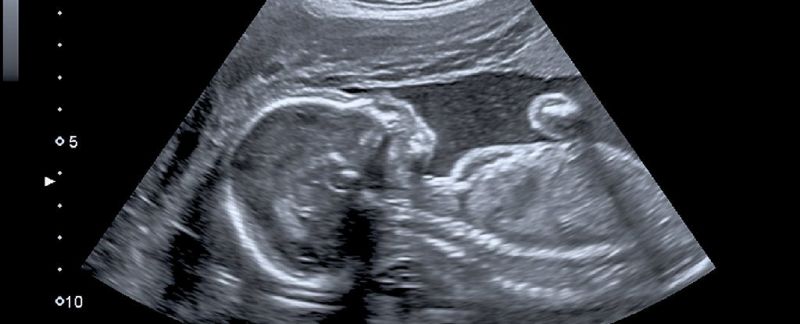

ਲੰਡਨ : (ਪੀਟੀਆਈ) ਲੰਡਨ ਵਿਚ ਮਾਂ ਦੀ ਕੁੱਖ 'ਚ ਹੀ ਬੱਚੇ ਦੀ ਸਪਾਈਨਲ ਸਰਜਰੀ ਕੀਤੀ ਗਈ। ਬੱਚੇ ਵਿਚ ਸਪਾਈਨਾ ਬਿਫਡਾ ਨਾਮ ਦੀ ਬੀਮਾਰੀ ਦਾ ਪਤਾ ਚਲਿਆ ਸੀ। 90 ਮਿੰਟ ਚੱਲੀ ਸਰਜਰੀ ਨੂੰ ਲੰਡਨ ਯੂਨੀਵਰਸਿਟੀ ਕਾਲਜ ਦੇ ਹਸਪਤਾਲ ਦੀ 30 ਡਾਕਟਰਾਂ ਦੀ ਇਕ ਟੀਮ ਨੇ ਅੰਜਾਮ ਦਿਤਾ। ਸਪਾਈਨਾ ਬਿਫਡਾ ਅਜਿਹੀ ਹਾਲਤ ਹੈ ਜਦੋਂ ਗਰਭ ਅਵਸਥਾ ਦੌਰਾਨ ਬੱਚੇ ਦੀ ਰੀੜ੍ਹ ਦੀ ਹੱਡੀ ਠੀਕ ਤਰ੍ਹਾਂ ਨਾਲ ਵਿਕਸਿਤ ਨਹੀਂ ਹੋ ਪਾਉਂਦੀ। ਰੀੜ੍ਹ ਦੀ ਹੱਡੀ ਵਿਚ ਇਕ ਦਰਾਰ ਬਣ ਜਾਂਦੀ ਹੈ। ਨਤੀਜੇ ਵਜੋਂ ਜਨਮ ਤੋਂ ਬਾਅਦ ਬੱਚੇ ਨੂੰ ਚੱਲਣ - ਫਿਰਣ ਅਤੇ ਸਿੱਧੇ ਖੜੇ ਹੋਣ ਵਿਚ ਮੁਸ਼ਕਿਲ ਹੁੰਦੀ ਹੈ।

Baby in Womb

ਬੱਚਾ ਦਿਮਾਗੀ ਤੌਰ 'ਤੇ ਵੀ ਕਮਜ਼ੋਰ ਹੋ ਸਕਦਾ ਹੈ। ਜ਼ਿਆਦਾਤਰ ਮਾਮਲਿਆਂ ਵਿਚ ਬੱਚੇ ਦੇ ਜਨਮ ਤੋਂ ਬਾਅਦ ਸਰਜਰੀ ਕੀਤੀ ਜਾਂਦੀ ਹੈ। ਡਾਕਟਰਾਂ ਨੇ ਸਪਾਈਨਾ ਬਿਫਡਾ ਨਾਲ ਪੀਡ਼ਤ ਦੋ ਬੱਚਿਆਂ ਦੀ ਸਰਜਰੀ ਕੀਤੀ। 26 ਹਫਤੇ ਦੀ ਪ੍ਰੇਗਨੈਂਸੀ ਵਿਚ ਗਰਭਵਤੀ ਮਹਿਲਾ ਨੂੰ ਸਰਜਰੀ ਤੋਂ ਪਹਿਲਾਂ ਏਨੇਸਥੀਸੀਆ ਦਿਤਾ ਗਿਆ ਸੀ। ਬੱਚੇਦਾਨੀ ਤੋਂ ਬਾਅਦ ਬੱਚੇ ਦੇ ਸਪਾਈਨ ਵਾਲੇ ਹਿੱਸੇ ਨੂੰ ਖੋਲ੍ਹਿਆ ਗਿਆ। ਬੱਚੇ ਦੀ ਪਿੱਠ ਦੇ ਹੇਠਲੇ ਹਿੱਸੇ ਵਿਚ ਰੀੜ੍ਹ ਦੀ ਹੱਡੀ ਮੁੜੀ ਹੋਈ ਸੀ। ਇਸ ਦੀ ਸਰਜਰੀ ਕੀਤੀ ਗਈ। ਆਪਰੇਸ਼ਨ ਤੋਂ ਬਾਅਦ ਮਹਿਲਾ ਦੀ ਆਮ ਗਰਭਵਤੀ ਦੀ ਤਰ੍ਹਾਂ ਡਿਲੀਵਰੀ ਹੋ ਸਕੇਗੀ।